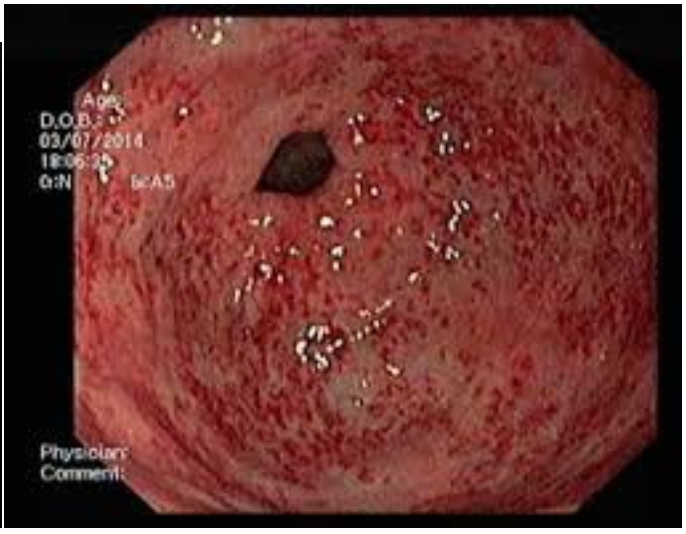

portal hypertensive gastropathy